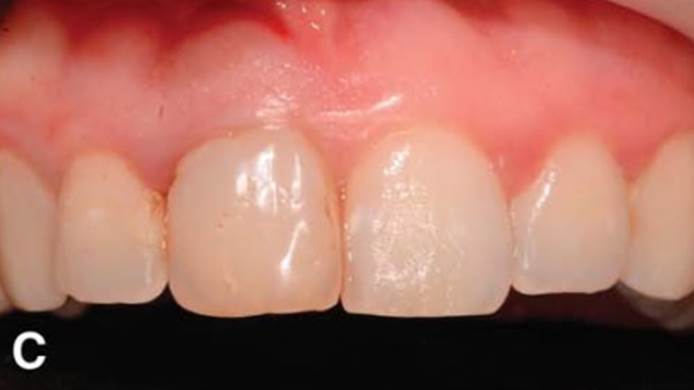

Clinical case: Immediate post-extraction insertion of implant & immediate loading

- Courtesy of Prof. Giuseppe Luongo, Italy -

AnyRidge, immediate loading, single implant, multicenter study, maxillary anterior, Prof. Giuseppe Luongo, single replacement

Clinical case: Replacement of fractured central incisor (#11) with immediate implant

& Root Membrane Technique

- Courtesy of Dr. Miltiadis Mitsias, Greece -